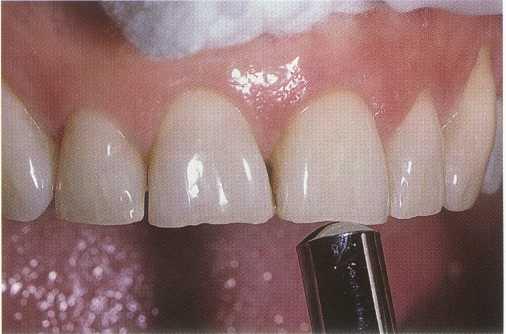

FIGURE 1-9 Electric pulp testing can be used to establish pulp vitality or confirm non responsiveness. In this case the failure of tooth #9 to respond confirms the results obtained with thermal testing.

ELECTRIC PULP TESTING. Electric pulp testing stimulates the A-delta nerve fibers. The electric pulp test (EPT) indicates only whether the pulp is responsive or unresponsive. It does not provide information regarding the health of the pulp, nor can it differentiate degrees of pulp pathosis other than to indicate necrosis when no response occurs." It is often used to confirm the results of previous tests. The EPT requires an isolated dry field. Traditionally the electrode is coated with a conducting medium, usually toothpaste, and placed on the dry enamel labial or buccal surface of the tooth to be tested (Figure 1-9). Evidence indicates that the incisal edge is the optimal placement site for the electric pulp tester electrode to determine the lowest response threshold. 16 Contact with metallic restorations is to be avoided. The Analytical Technology (Analytic Endodontics, Sybron Dental Specialties, Orange, CA) pulp tester is recommended because it begins at zero current and increases the current gradually at a rate predetermined by the op-

erator.17 Patients are instructed to place a hand on the metal handle to begin the test and release the handle when they perceive a tingling sensation to stop the test. Having control of the test is reassuring to the patient. As with other tests, the clinician should test a normal tooth first to familiarize the patient with the procedure and sensation.